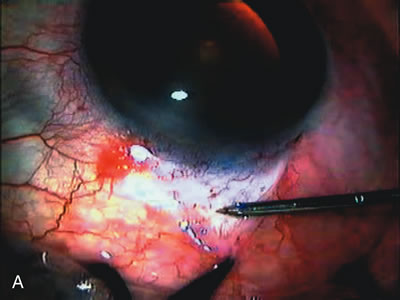

Fig. 1. The anatomic advantage of small incision cataract surgery for the glaucoma patient. A. Long-term bleb function with a large cataract incision is difficult to achieve with either ECCE-trabeculectomy or trabeculectomy followed later by ECCE. This bleb failed to form sufficiently when combined with large incision ECCE. The inflammation, bleeding, and long-term wound healing with stimulation of fibroblasts associated with this technique are more likely to cause bleb failure. In addition, the increased iris manipulation necessary to deliver the nucleus and subsequent iris repair adds to the long-term breakdown of the blood aqueous barrier. B and C. Two-site phacotrabeculectomy has the advantage of small incision cataract surgery combined with separate site trabeculectomy. The incision size is one third the size of the standard ECCE. The inflammation is less severe, and cataract wound healing is confined to the temporal area. Visual rehabilitation with phacoemulsification and foldable IOL is much faster. Phacoemulsification allows successful lens extraction even in the unfriendly environment of a smaller pupil compared with ECCE. The trabeculectomy is performed in an entirely different site, well away from the wound healing associated with temporal phacoemulsification. The likelihood of this filter functioning long-term is greater than with ECCE-trabeculectomy. D. The surgeon also has the option of single-site phacotrabeculectomy with foldable IOL. Both the lens extraction and trabeculectomy are performed through one small 3.5-mm limbal incision.

In years past, patients with both cataract and glaucoma frequently provided overwhelming surgical challenges for the ophthalmologist. The ability to carry out phacoemulsification through a 3.2-mm corneal incision along with inserting a foldable IOL is a vast improvement over 11-mm incisions that were common a decade ago (Fig. 1). The anatomical and inflammatory changes to the eye are less with small incision techniques, improving the likelihood of success with concomitant glaucoma surgery. Pharmacologic inhibition of fibrosis along with postoperative wound revision increases the long-term success rate of filtration surgery when combined with lens extraction. (Fig. 2). The learning curve may be steep at times, but the blending of cataract and glaucoma surgical skills slowly falls into place as the surgeon constantly learns and upgrades his or her technique.